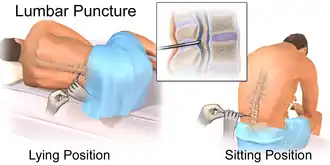

Ponction lombaire

La ponction lombaire est un geste médical permettant un prélèvement de liquide cérébrospinal. Le patient est positionné soit en décubitus latéral, soit en position assise, rachis en flexion. Une aiguille adéquate est insérée après avoir effectué une anesthésie locale. Ce geste permet de mesurer la pression d'ouverture de l'espace sous arachnoïdien, en utilisant un manomètre dès que l'aiguille est en place. Sa valeur est normalement comprise entre 6 et 18 cm d'eau[27] ; elle est habituellement élevée en cas de méningite bactérienne[10],[26], ou à cryptocoque[30]. La description macroscopique du liquide peut orienter vers la nature de l'infection : un aspect opaque indique un niveau élevé de protéines, hématies, leucocytes ou bactéries, ce qui peut suggérer une origine bactérienne[10].